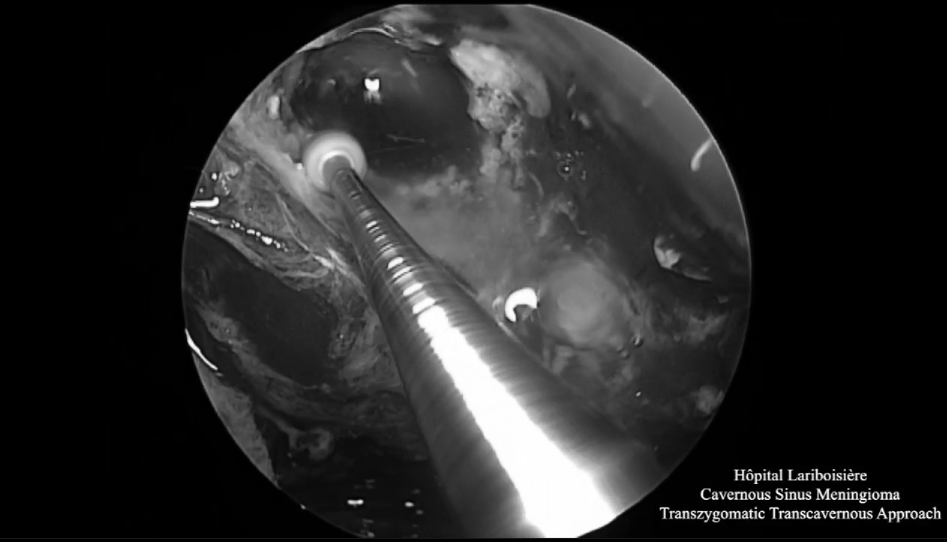

▼显微镜下切除部分肿瘤或瘤内减压

▼显微镜下暴露充分肿瘤,进行关键解剖定位